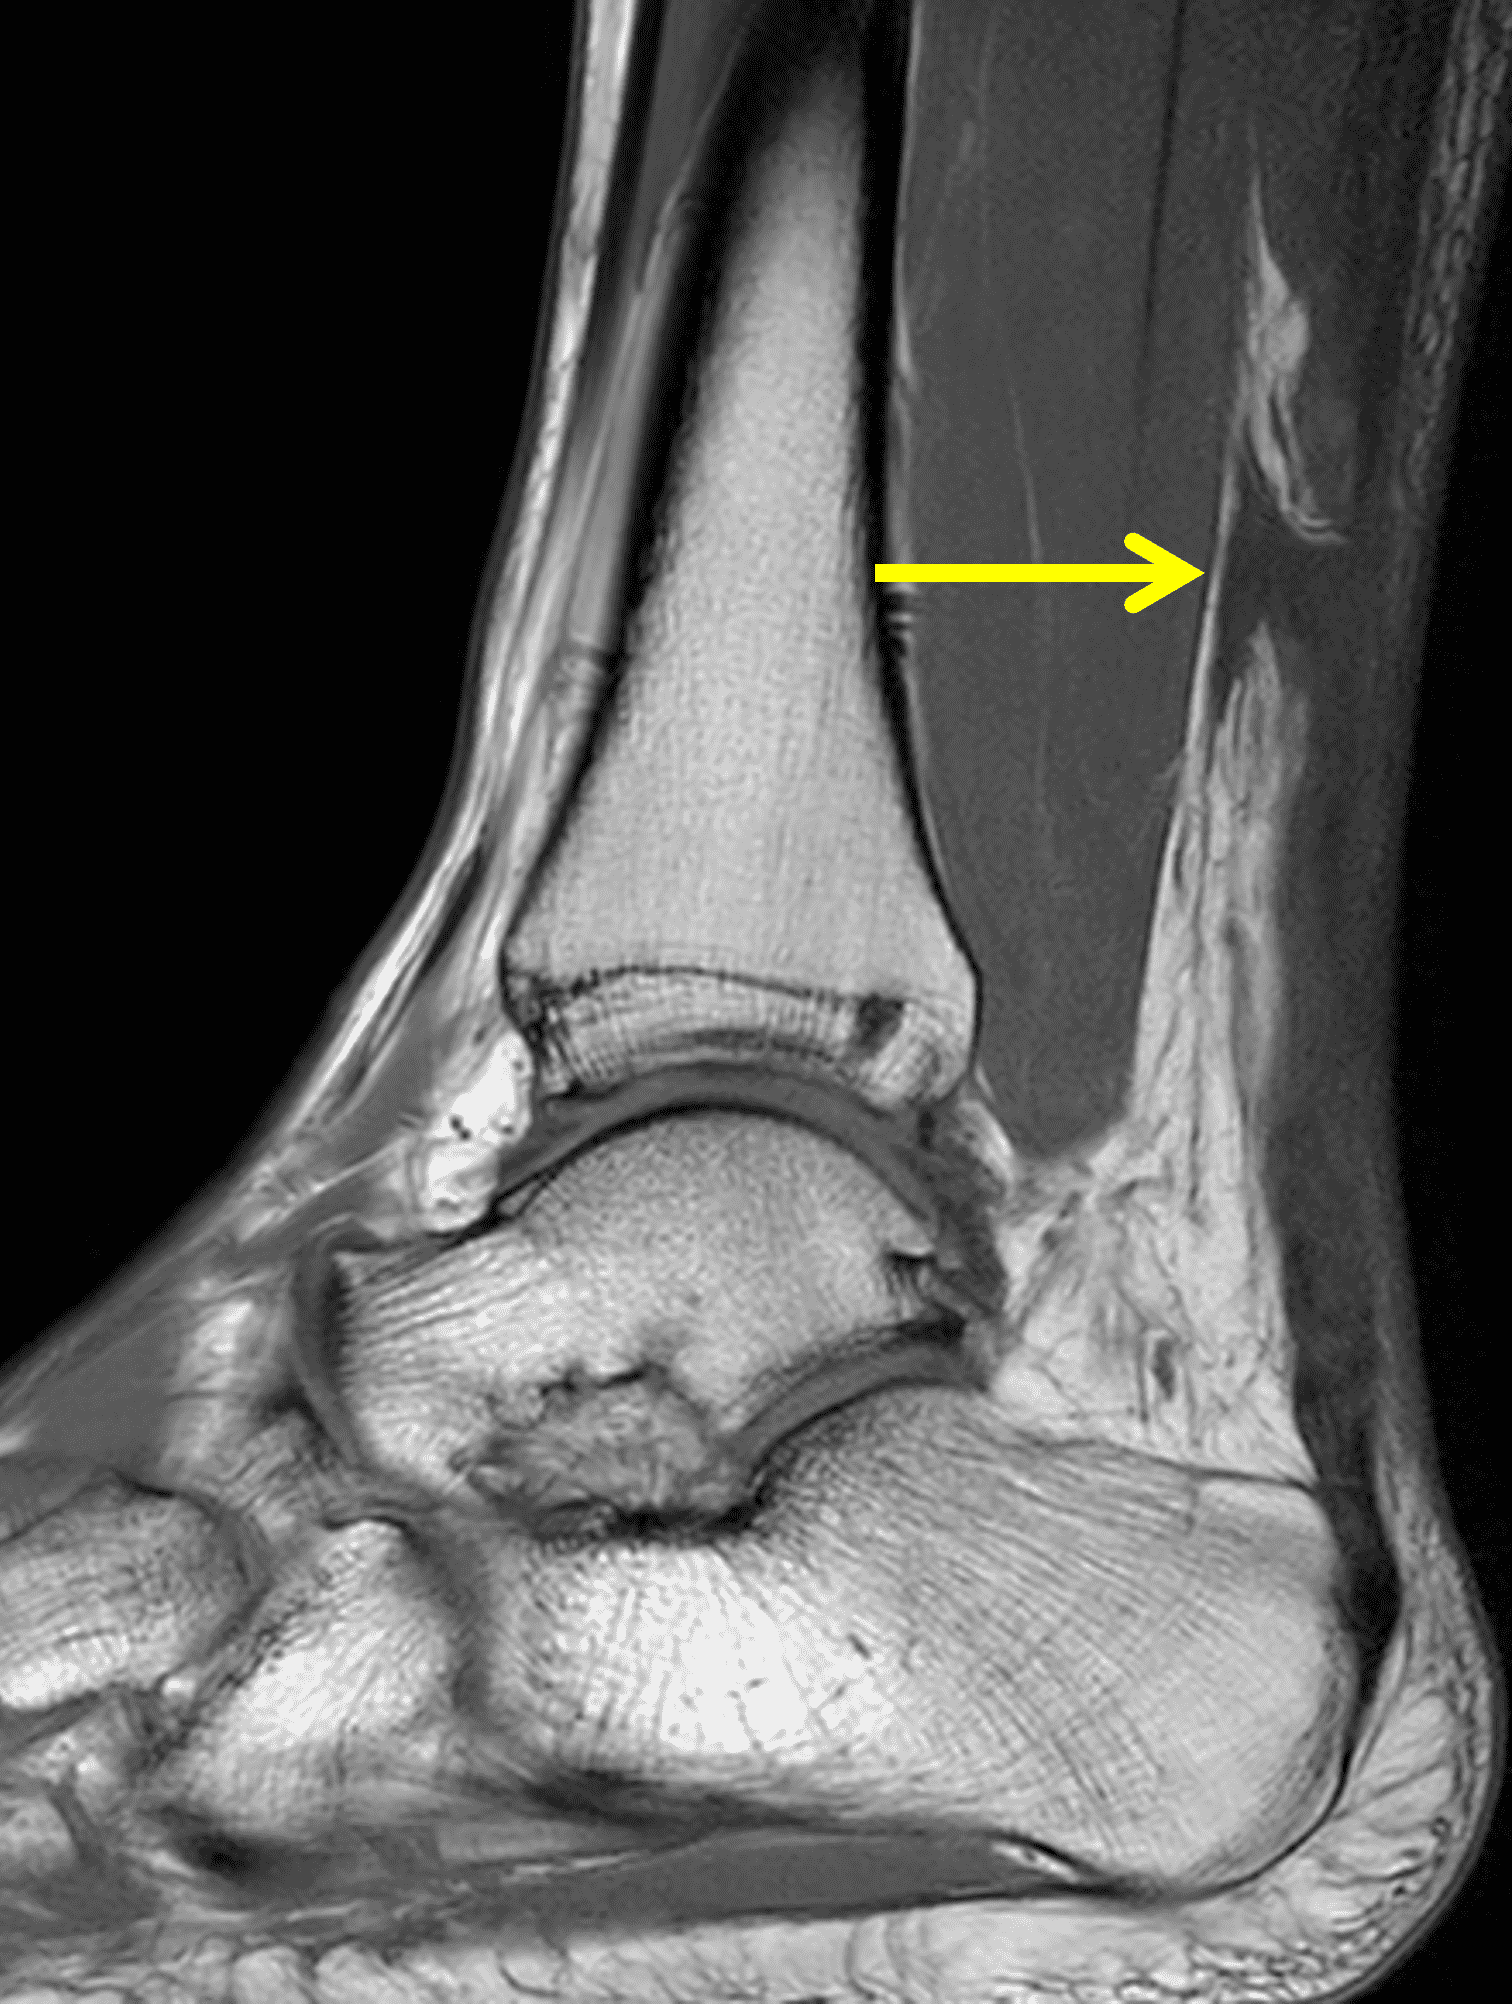

A 22 year-old male college football player presents with a “pop” and pain posterior to the right ankle during practice 1 week prior. He is unable to bear weight. Lateral radiograph (1A), sagittal fat-suppressed T2-weighted (1B), sagittal T1-weighted (1C), and transverse fat-suppressed T2-weighted images are provided. What is your diagnosis? What MRI findings affect clinical management decisions?

Figure 2: Complete Achilles tendon rupture. (2A) The lateral radiograph shows a thick and indistinct proximal Achilles tendon contour (arrows). (2B) A fat-suppressed T2-weighted image shows complete rupture of the tendon with a fluid-filled gap (yellow arrow) measuring 1.5 cm in length, located 10 cm cranial to the tendon insertion (blue arrow) and just distal to the edematous myotendinous junction (red arrow). The tear is superimposed on diffuse tendinosis. (2C) A sagittal T1-weighted image confirms the diffuse tendinosis. Fluid extends anteriorly into Kager’s fat pad (arrow) suggesting disruption of the anterior paratenon. (2D) A transverse fat-suppressed T2-weighted image through the proximal tendon shows no intact fibers (arrow), confirming the full-thickness rupture.